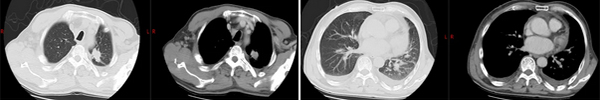

治疗前(2020年6月)

治疗5年(2025年6月)